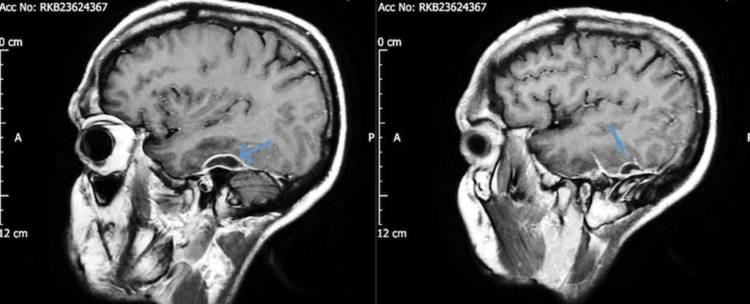

Lo más inquietante fue que el hombre relató que durante cinco años padeció un dolor intermitente en el oído izquierdo y estaba perdiendo la audición. Cuando los médicos realizaron una tomografía, encontraron en el paciente abscesos en el tejido que rodeaba su cerebro.

La bacteria culpable de la infección fue la Pseudomonas aeruginosa, un patógeno que causa todo tipo de enfermedades y que ocasionó otitis extrerna necrotizante dañando el tejido que se encuentra en el canal auditivo externo.

Esta bacteria llegó al cráneo a través de un pedazo de algodón que formaba parte de un cotonete, el cual se había quedado atascado en la cabeza del paciente durante años.